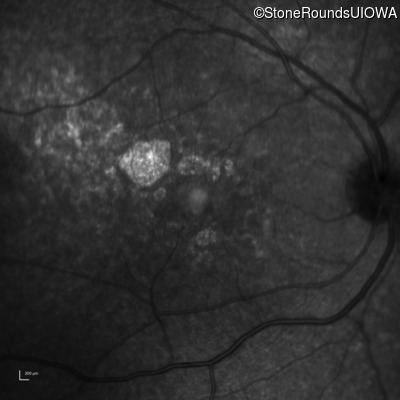

Age at visit: 30 years

This 30 year old man first noticed poor vision in dim light when he was five years old. His visual acuity began to fall in his early 20's.

Macular Disease WDR19 His344Arg CAT>CGT Ser485Ile AGT>ATT AR